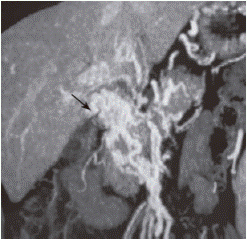

КТ может дать информацию о состоянии стенок сосудов, поражении печени (например, с формированием узлов) и показать протяженность тромбоза. (см. Рисунок 2).

Рисунок 2. КТ с ангиографией портальной системы. Стрелка показывает каверноматозную трансформацию вокруг затромбированной воротной вены и порто-системные коллатерали.